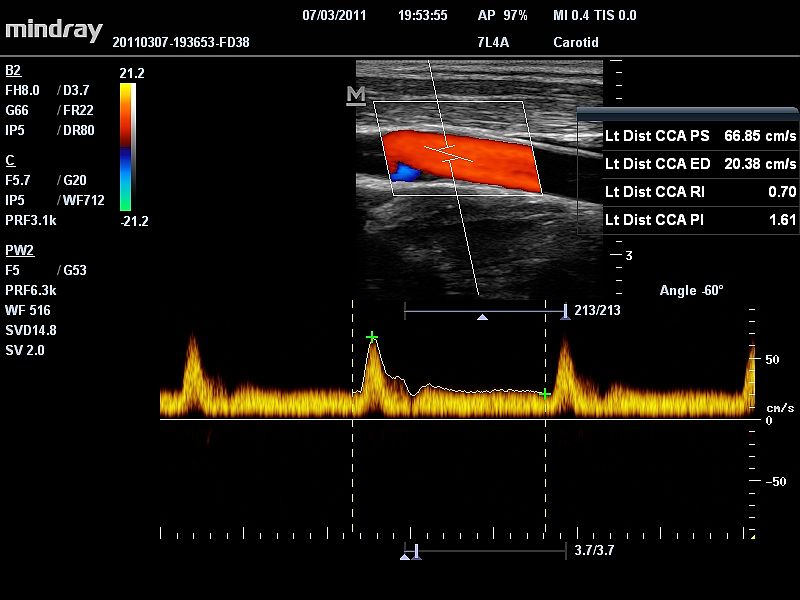

PW – режим импульсно-волнового допплера

Режим импульсно волнового допплера (pulse wave Dopper – PW) – режим, работая в котором мы пытаемся избавится от главного недостатка режима CW, а именно отсутствия пространственного разрешения (разрешающей способности по глубине). Импульсные сигналы (короткие по времени) позволяют оценить отдельные зоны по глубине, поэтому в процессе работы на ультразвуковом приборе нам необходимо выбрать зону интереса (окно опроса). Конечно же и здесь не обошлось без недостатков – главным недостатком использования режима импульсно-волнового допплера является строгое ограничение по измерению больших скоростей на больших глубинах сканирования.

6151b02ec584d67b38dddf69bc0955ec89f95561.jpg